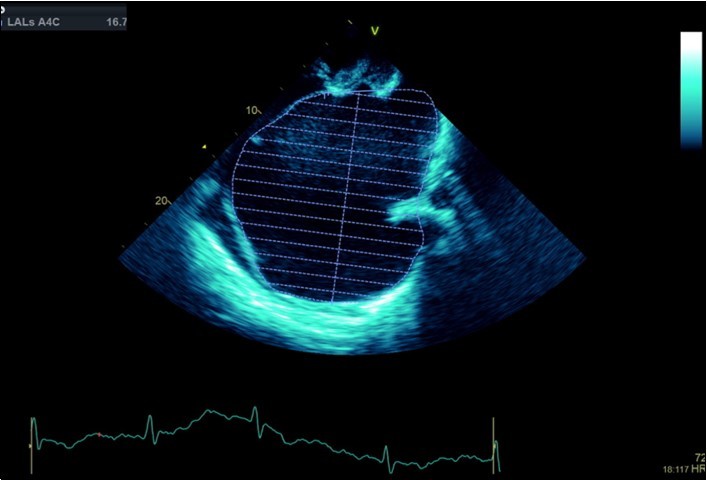

A dramatically dilated left atrium was seen on a TTE (see Figure 2a, Figure 2b, Figure 2c, and Figure 2d). Severe mitral stenosis with associated regurgitation was evident, with a mean gradient across the valve of 11mmHg and a hyperdynamic left ventricle. The left atrial volume measured by Simpson’s biplane method (see Figure 2c) was 2108mL, or 1548.5 ml/m2, based on height 1.55 metres and weight 44 Kg. Normal left atrial volume in a woman is 16 - 34 ml/m21. The computed tomography scan (CT) chest AP view (see Figure 3) is also shown.

Figure 2c.Transthoracic echocardiogram Apical 4C view. Left atrial size estimation by Simpson’s biplane method from apical 4C view.

Figure 2d.Transthoracic echocardiogram Apical 2C view. Left atrial size estimation by Simpson’s biplane method from apical 2C view. Severely enlarged left atrium (estimated 2108ml, 1548.5ml/m2)

Massive left atrial dilatation is a recognized phenomenon in chronic mitral stenosis, and is considered by some to be protective against the development of pulmonary oedema in mitral regurgitation 2. Left atrial dilatation to this extent is not usually seen in living patients, however. The largest described left atrium was 3000 ml at autopsy, with another measuring 1760 ml at autopsy in 19313. Other reports in living patients include a left atrium that was estimated at approximately 2000ml on magnetic resonance imaging 4.The more precise measurements for the left atrial size we recorded on cardiac ultrasound have not been described previously. Considering the size of the left atrium, it is surprising that the mean gradient across the mitral valve was only 11mmHg. Although this is certainly severe, it could be expected that a gradient would be higher based on the severity of the left atrial dilation. We hypothesize that the gradient may have been greater previously, however the massive dilation of the left atrium may have subsequently led to a dilation of the mitral annulus, leading to an improvement in the mitral valve effective orifice area, and hence a reduction in the severity of the mean mitral valve gradient.